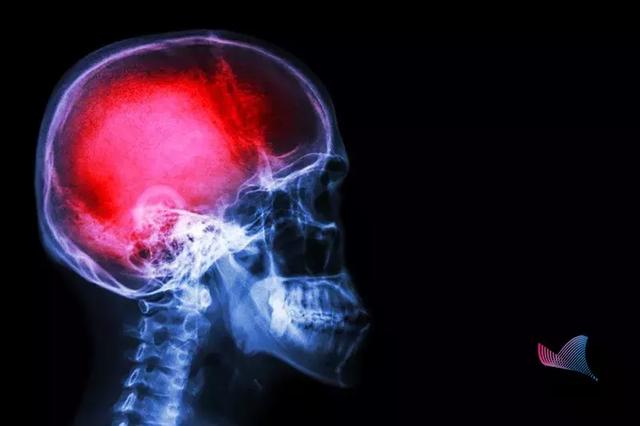

中风

第一杀手,是造成中国人寿命损失的第一大病因。据WHO数据显示,我国脑卒中的发生率位居世界第一。

我国每年脑卒中发生病例500余万,其中约有196万人死亡。

脑卒中,又称中风,很多人对中风的认识只是停留在患者会口眼歪斜、口齿不清。

什么是脑卒中?

当附着在血管壁的栓子脱落,堵塞脑部血管时,形成缺血性中风。而当脑血管破裂,颅内出血时,就会形成出血性中风。